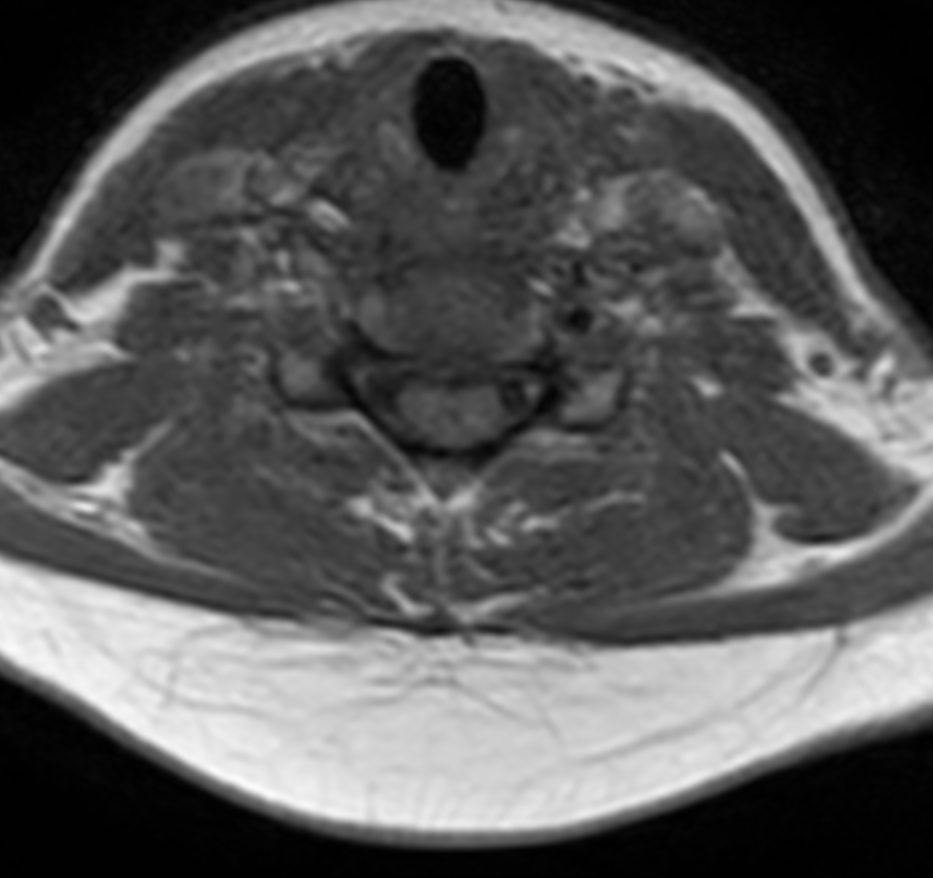

Axial mFFE (small FOV)